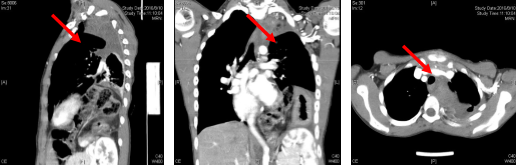

(术后CT复查,“→”表示肿瘤残腔)